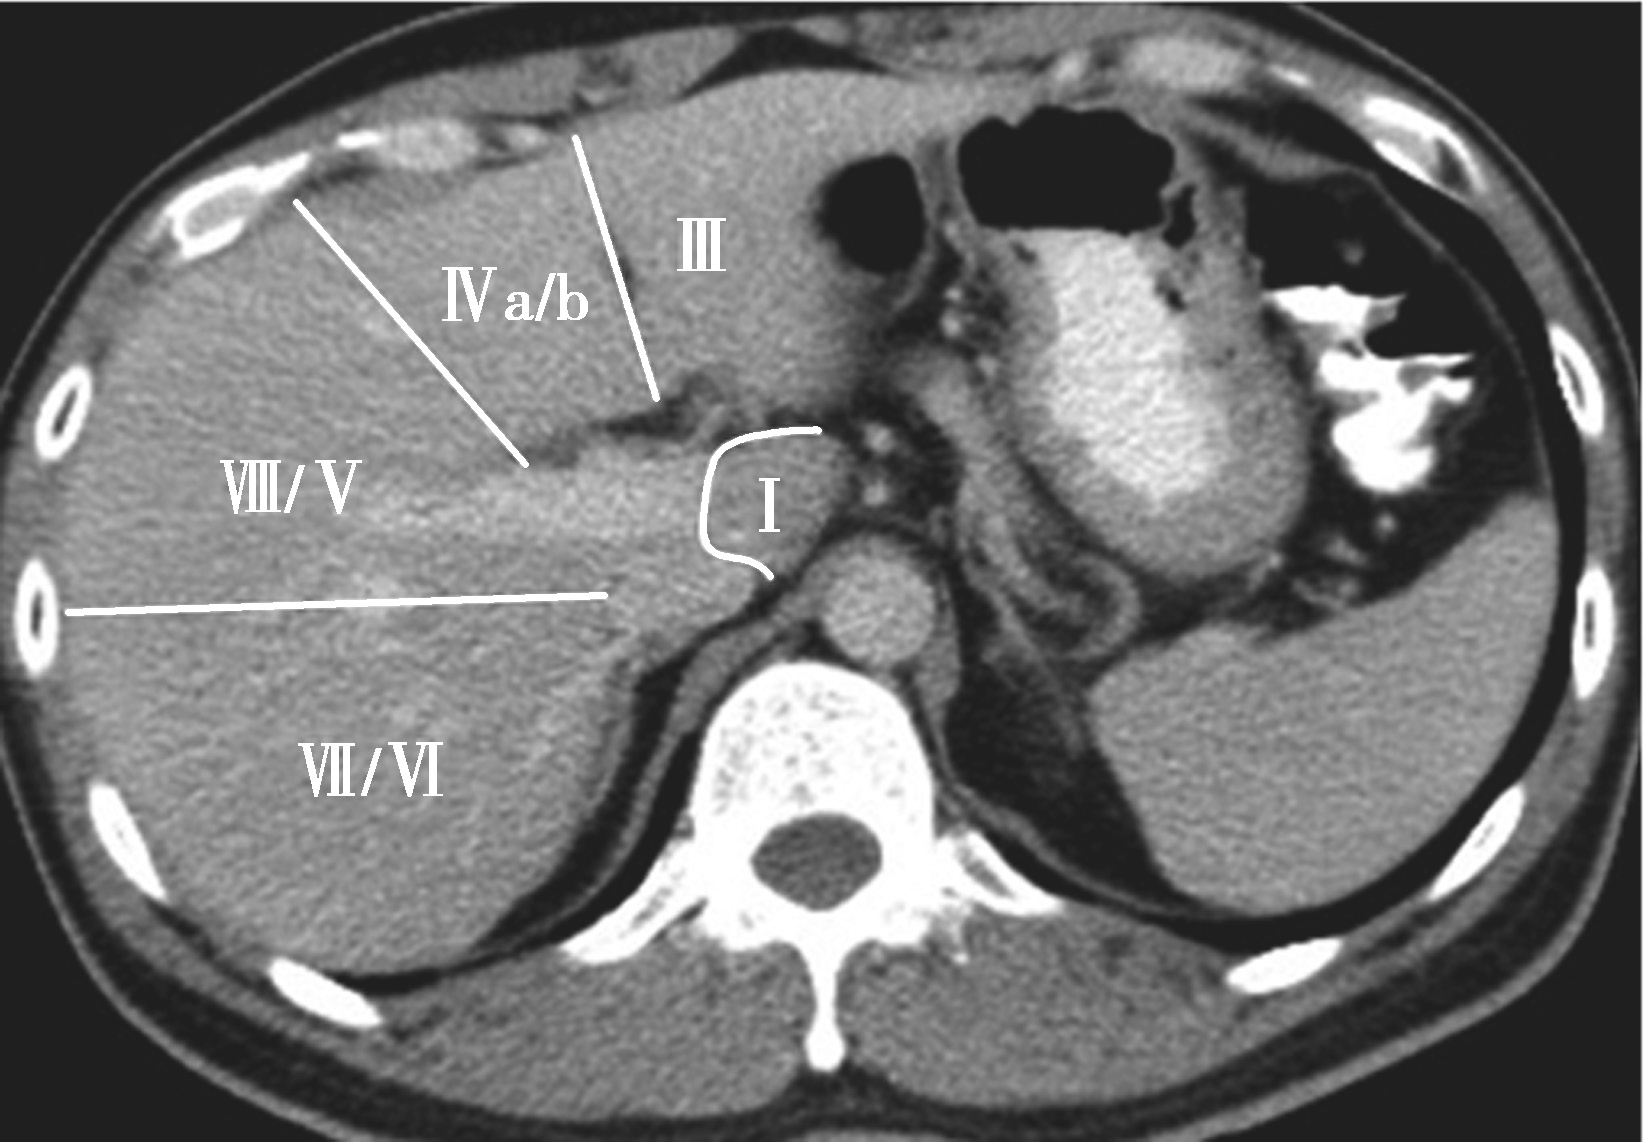

(3)肝8段划分法(图5-21-35):

Couinaud根据门静脉及肝静脉的分布将肝脏分为8段,门静脉分布于肝段内,肝静脉分布于肝段间。8分段法是临床外科和影像最为常用的分段法。以肝中静脉为界分为左、右半肝;以肝左静脉为界将左半肝分为左内(Ⅳ段)和左外叶(Ⅱ段+Ⅲ段);左外叶以门静脉左支为界水平分为上(Ⅱ段)下(Ⅲ段)两段;以肝右静脉为界分右半肝为前叶(Ⅷ段+Ⅴ段)和后叶(Ⅵ段+Ⅶ段);以门静脉右支为界将右肝横向分为上下两段分别为右前上段(Ⅷ段)、右前下段(Ⅴ段),右后下段(Ⅵ)和右后上段(Ⅶ段);肝尾状叶为单独一段(Ⅰ段)。

图5-21-35 肝8段划分法示意图